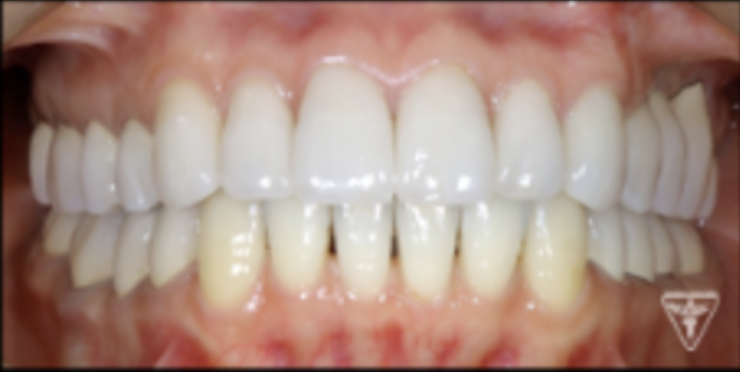

最終補綴物装着時

治療後

治療前後の比較